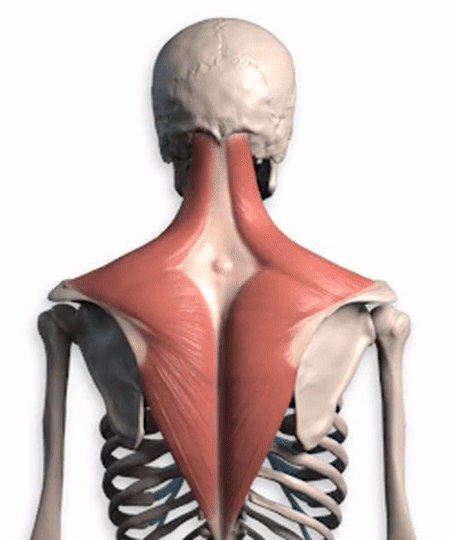

Viele meiner Freunde denken, dassDer Nacken ist der Nacken, die Schultern sind die Schultern, der Rücken ist der Rückendass die drei nicht viel miteinander zu tun haben, in Wirklichkeit ist diese Idee voreingenommen, von den Medizinstudenten, wir sollten die颈, Schulter, RückenBetrachten Sie ihn als einen einzigen Muskel und geben Sie eine kurze Analyse dieses Muskels, nämlich desTrapezmuskel (des oberen Rückens und des Halses)。

Wenn Sie genau hinschauen, sehen SieDieser Trapezius.einschließen.Schädelbasis, Nacken, Schultern und RückenDie Trapezmuskeln auf beiden Seiten sind eng miteinander verbunden und bilden zusammen eine rhomboide Struktur, die für die Aufrechterhaltung des Gleichgewichts wichtig ist.Stabilisierung des RückensSie spielt eine sehr wichtige Rolle bei der Bewältigung zahlreicher Tätigkeiten im Nacken-, Schulter- und Rückenbereich und wird in der Medizin alsDer Trapeziusmuskel ist in ein oberes, mittleres und unteres Bündel unterteilt, und die verschiedenen Teile der Kontraktion führen unterschiedliche Bewegungen aus。

Das ist nur ein Muskel, es gibt noch viele weitere im Nacken, in den Schultern und im Rücken.Fleischdie alle miteinander verbunden sind, einschließlichFaszien unter der HautEs ist auch alles ein und dasselbe, wir können den Nacken, die Schultern und den Rücken nicht trennen, ich glaube, das sollten wir verstehen.